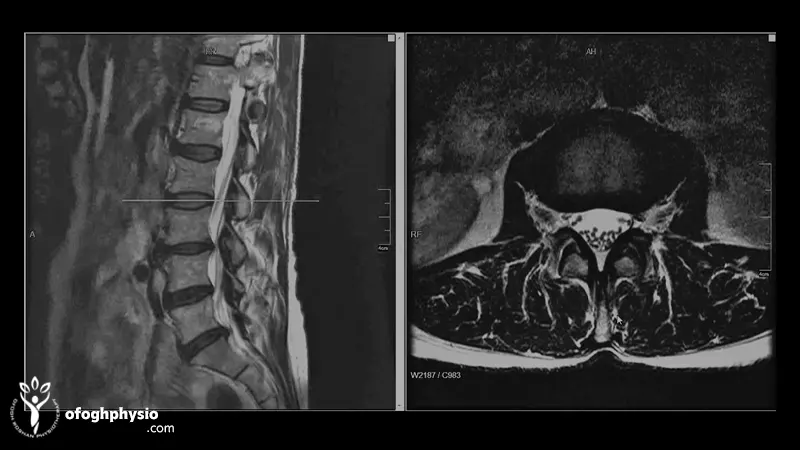

إذا كان هناك احتمالية لبروز القرص بناء على الفحص فإن الخطوة التالية هي التصوير بالرنين المغناطيسي. التصوير بالرنين المغناطيسي هو أفضل طريقة لمعرفة حالة الطبقة الخارجية للقرص (الحلقة الليفية) والطبقة الهلامية بداخلها (Nucleus Pulposus) وكمية البروز وهل هناك ضغط على جذور الأعصاب أم لا. وفي بعض الحالات الخاصة، يتم أيضًا استخدام الأشعة المقطعية أو مخطط كهربية العضل؛ يتم استخدام مخطط كهربية العضل (EMG) عندما يريد الأخصائي فحص درجة تلف الأعصاب بشكل أكثر دقة.